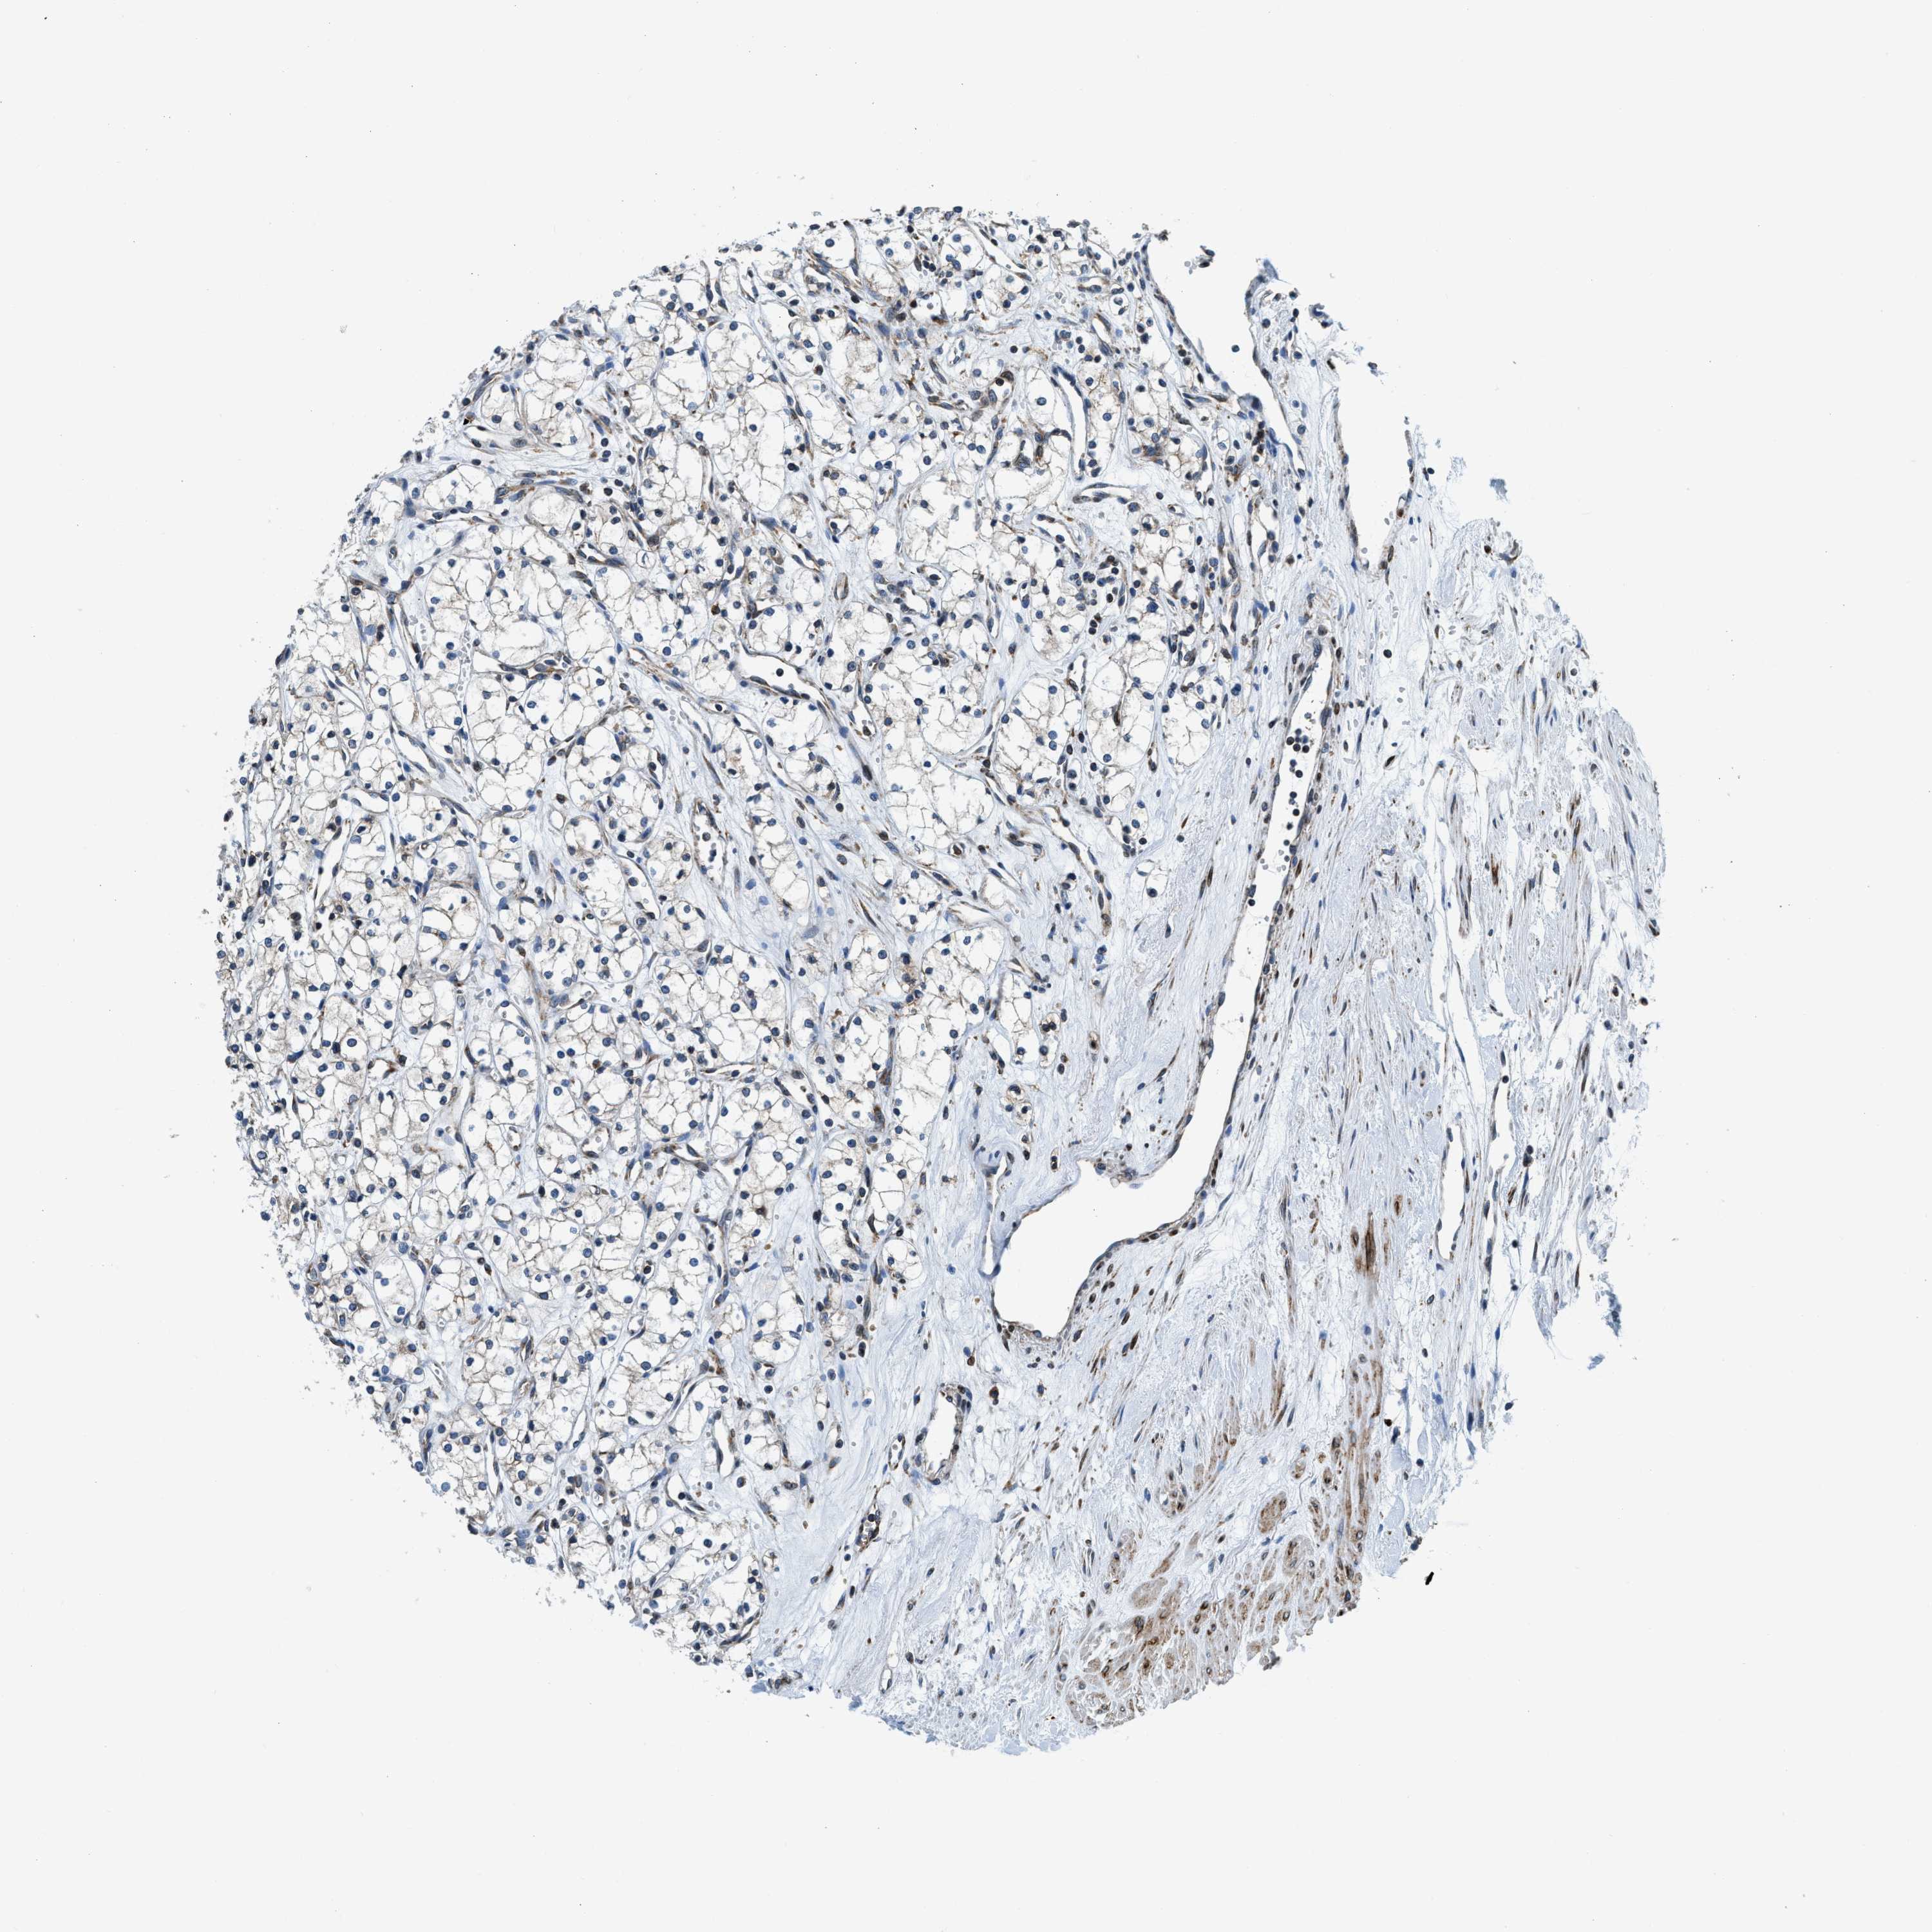

KIDNEY RENAL PAPILLARY CELL CARCINOMA (TCGA) - Interactive survival scatter ploti

The Survival Scatter plot shows the clinical status (i.e. dead or alive) for all individuals in the patient cohort, based on the same data that underlies the corresponding Kaplan-Meier plots. Patients that are alive at last time for follow-up are shown in blue and patients who have died during the study are shown in red.

The x-axis shows the expression levels (FPKM) of the investigated gene in the tumor tissue at the time of diagnosis. The y-axis shows the follow-up time after diagnosis (years). Both axes are complimented with kernel density curves demonstrating the data density over the axes. The top density plot shows the expression levels (FPKM) distribution among dead (red) and alive patients (blue). The right density plot shows the data density of the survived years of dead patients with high and low expression levels respectively, stratified using the cutoff indicated by the vertical dashed line through the Survival Scatter plot. This cutoff is automatically defined based on the FPKM cutoff that minimizes the p-score. The cutoff can be changed by dragging the vertical line or by entering a cutoff value in the square labeled "Current cut-off".

Under the Survival Scatter plot the p-score landscape (black curve; left axis) is shown together with dead median separation (red curve; right axis). Dead median separation is the difference in median mRNA expression between patients who have died with high and low expression, respectively. It is calculated as follows: median FPKM expression of dead patients with high expression - median FPKM expression of dead patients with low expression. This is intended to aid the user in visually exploring custom cutoffs and the associated p-scores and dead median separation.

Individual patient data is displayed and can be filtered by clicking on one or more of the category buttons on the top of the page. Categories describing expression level and patient information include: high, low, alive, dead, female, male and tumor stages. The scale of the x-axis can be toggled between linear and log-scale by clicking on the "x log" button. Mouse-over function shows TCGA ID, patient information and mRNA expression (FPKM) for each patient.

& Survival analysisi

Kaplan-Meier plots summarize results from analysis of correlation between mRNA expression level and patient survival. Patients were divided based on level of expression into one of the two groups "low" (under cut off) or "high" (over cut off). X-axis shows time for survival (years) and y-axis shows the probability of survival, where 1.0 corresponds to 100 percent.

CDS2 is not prognostic in Kidney Renal Papillary Cell Carcinoma (TCGA)